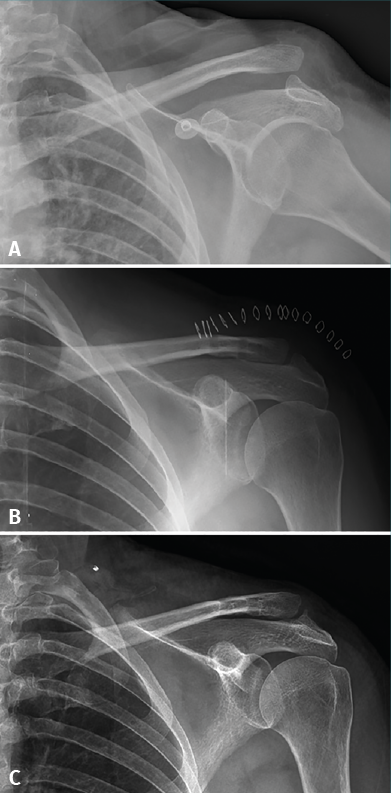

Figure 3. A 52-year-old woman with type IV acromioclavicular dislocation (A) subjected to surgery four weeks after injury due to refractory pain and dysfunction. The surgical outcome was considered acceptable, though with insufficient reduction (B). Fourteen months after surgery, the patient suffered persistent symptoms and loss of reduction was seen to have progressed (C).